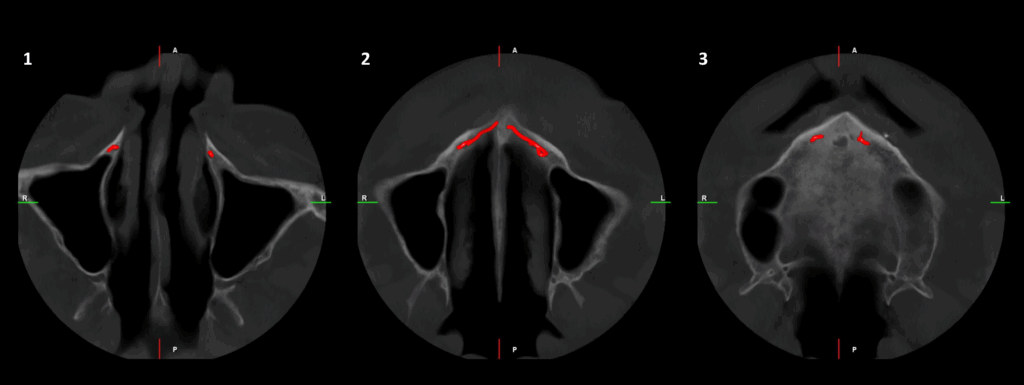

CORTES CORONALES

En el estudio complementario mediante tomografía computarizada de haz cónico (TCHC), se identifica la presencia del canalis sinuosus en el maxilar derecho, con trayecto que se dirige hacia la región ósea palatina correspondiente a las piezas 12 y 11. Asimismo, se evidencia un canalis sinuosus en el maxilar izquierdo, que se origina en la pared lateral de la fosa nasal izquierda y se dirige hacia la región ósea palatina y apical de las piezas 21 y 22.

Adicionalmente, se observa fractura radicular en la pieza 12, asociada a una imagen osteolítica periapical. Se identifican también fracturas radiculares con desplazamiento en las piezas 21 y 22. En la región correspondiente a la pieza 23, se evidencia un fragmento dentario sobre la cortical ósea vestibular.